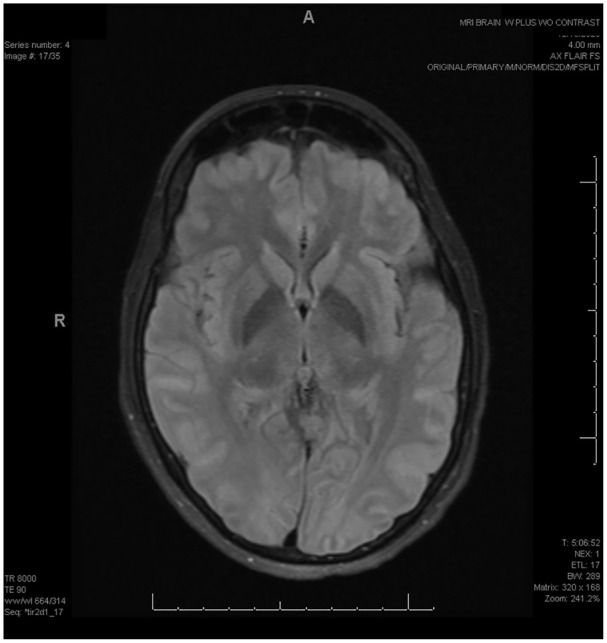

Hyperammonemia syndrome and posterior reversible encephalopathy syndrome (PRES) are potentially devastating diagnoses in transplant patients. Their underlying etiologies and pathophysiologies remain incompletely understood, and while they are separately well-documented complications in posttransplant patients, they have not been described concurrently. Here we present a case of both hyperammonemia syndrome and PRES causing rapid mental status decline in a 31-year-old bone marrow transplant recipient. The patient had extensive testing to rule out other diagnoses and made a full recovery after correction of her hyperammonemia. Further research is needed to elucidate the underlying mechanisms of these disease processes; however, clinicians should keep both diagnoses in mind when treating transplant patients with acute neurologic changes.